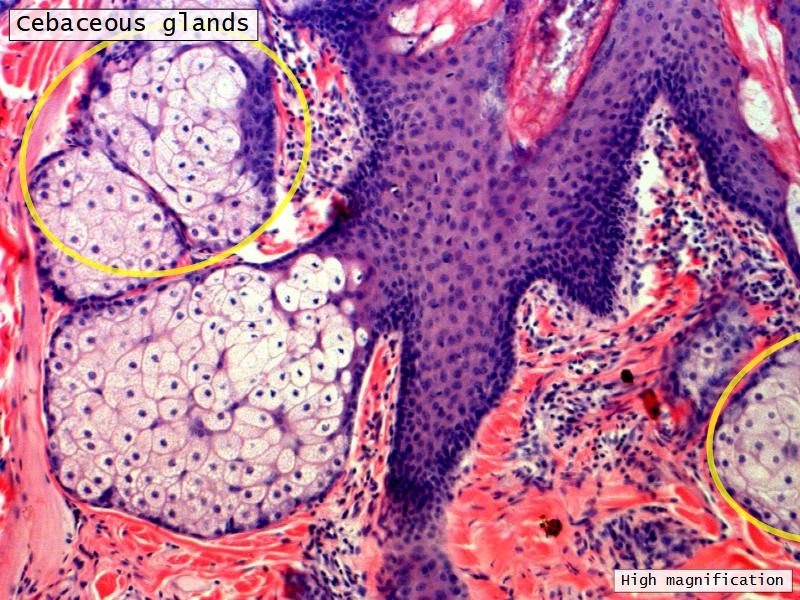

Nostril